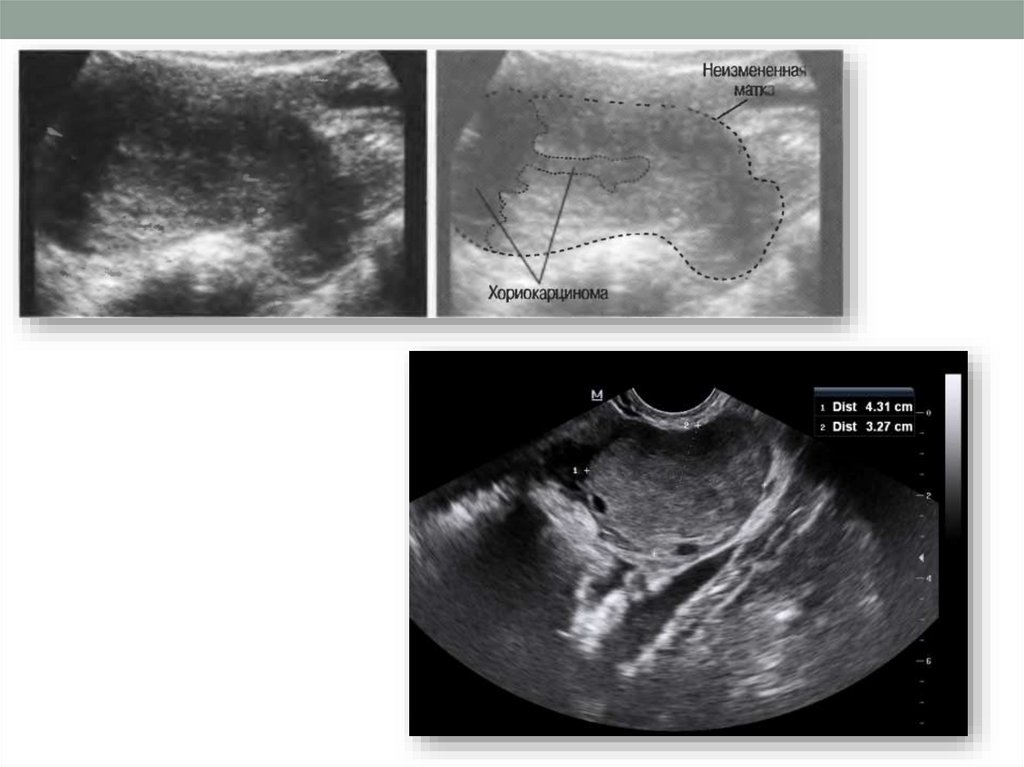

• ультразвуковом исследовании — обнаружение узлов

хорионэпителиомы.